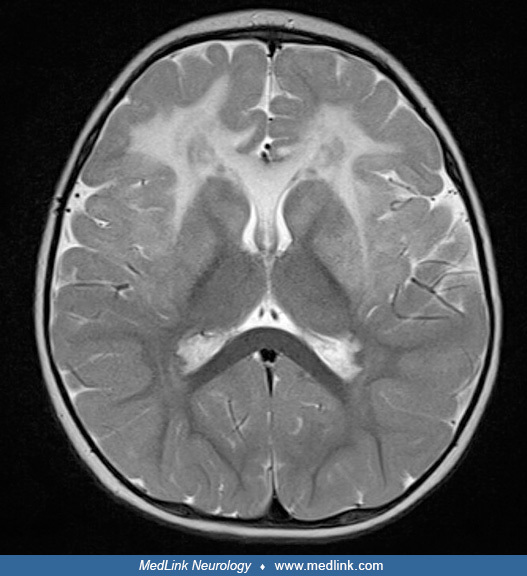

panda sign

symmetric hyperintensities of putamen > caudate, thalamus, brainstem; red nuclei are eyes

wilson’s disease

from copper deposition